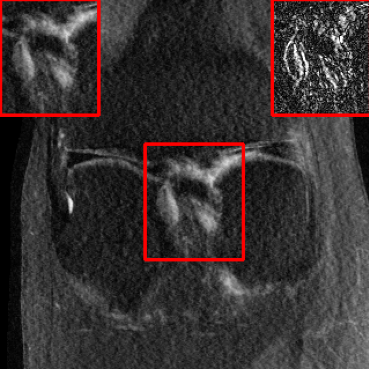

Results for the DIDN-based Reconstructor: To demonstrate adaptability to different network architectures, Table II compares reconstruction performance on the test set with the DIDN denoiser-based MoDL architecture. Average PSNR values with LONDN-MRI are compared to those with networks trained globally at different training set sizes. We ran only iteration of LONDN-MRI, where the reconstruction with a pre-trained (global) network was used to find neighbors. PSNR values for the oracle LONDN-MRI reconstructor are also shown. The overall performances with the DIDN-based architectures are better than with the UNet-based unrolled networks. The PSNRs for LONDN-MRI are consistently and similarly better than for the globally trained network across the different training set sizes considered, indicating potential for LONDN-MRI in improving state-of-the-art models. Fig. 6 visually compares reconstructions and reconstruction errors (in zoomed in region) for different methods. We can see that the LONDN reconstructors capture the original image features more sharply and accurately than the globally learned reconstruction.

| Ground Truth | Global | LONDN-MRI | Oracle |

| (1 iteration) | |||

![]() |

| PSNR = dB | PSNR = 34.15 dB | PSNR = 34.46 dB | PSNR = 34.54 dB |